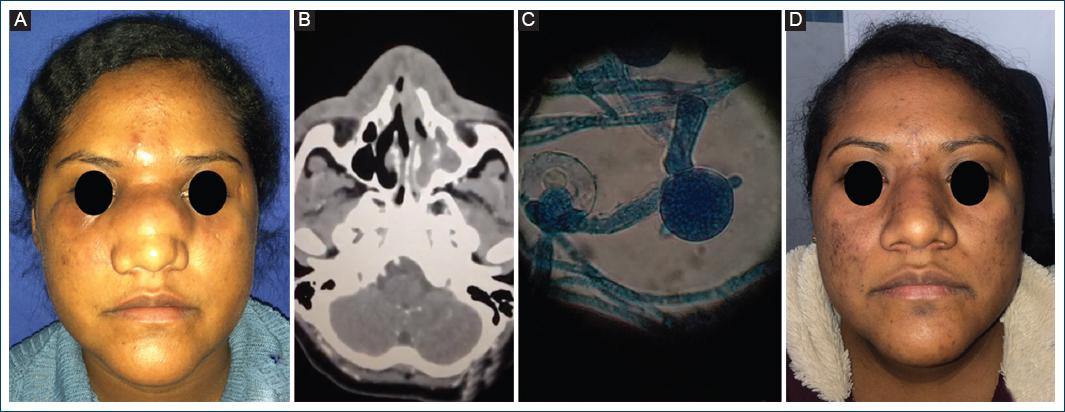

Second case

A 32-year-old woman, no significant medical history, working in the banking sector, resident in Mexico City, she was referred to our practice with a 20-day clinical condition regarding an intermittent bilateral nasal obstruction, with no predominant laterality, purulent anterior rhinorrhea, which was treated empirically with oral ciprofloxacin without improvement of symptoms. Later on, patient reported an increase in the centrofacial volume that involved the glabella and the nasal dorsum (Fig. 2A). The tomography showed increased density of the tissues of the nasal dorsum and non-specific mucosal thickening (Fig. 2B). The glabella was biopsied in the operating theatre and was subjected to mycological analysis, which revealed C. coronatus. Like the first patient, she was classified as a Stage I disease and was treated with TMP/SMZ for 10 days. She was later prescribed oral itraconazole at a reduced dose for 10 months. Improvement was clinically evident at 2 months (Fig. 2C).

Figure 1 A: patient #1 with nasal tumor of 1-year evolution. B: nasal tomography showing occupation of maxillary sinus, middle meatus, left ethmoid air cells and soft tissue infiltration. C: Classic appearance of Conidiobolus coronatus (broad pauciseptate hyphae). D: Evident clinical improvement after 6 months of treatment.